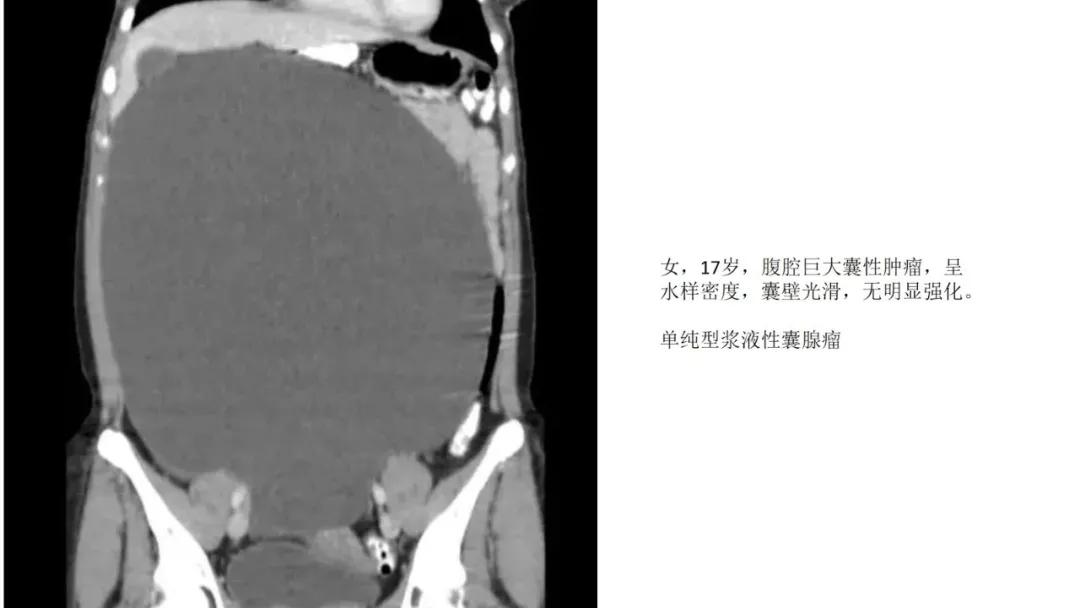

上皮性肿瘤:最常见,恶性多(卵巢癌),良性少。好发于50Y以上,发现时多为中晚期。多呈囊性或以囊性为主的囊实性肿块,完全实性者少见。形态多数不规则,边界模糊,囊壁及房间隔常不规则增厚,菜花样肿物或壁结节,囊实性区域分界不清,实性肿瘤常有不规则低密度或坏死区,可有边界模糊沙粒状或块状钙化,中-高度强化。良性者边界清晰,囊壁薄光整,无壁结节,实性部分呈无或轻度强化。